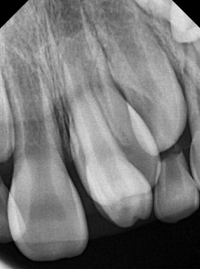

과잉치의 존재는 주변 치아의 정상적인 발육을 방해할 수 있으며, 경우에 따라서는 통증을 유발하거나 치아 배열의 이상을 초래할 수 있습니다. 진단은 주로 치과 엑스레이를 통해 이루어지며, 치료는 과잉치의 위치와 환자의 상태에 따라 다릅니다. 일반적으로는 외과적 발치가 필요할 수 있으며, 이후에는 교정 치료를 통해 정상적인 치열을 유지합니다.

-역위: 다른 치아와 반대방향으로 거꾸로 올라가는 방향으로 나는 과잉치를 의미합니다. (맨 위 사진)